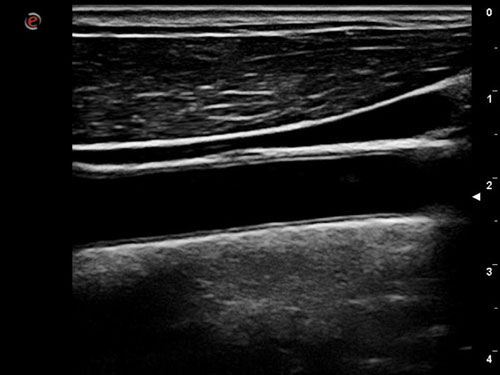

Viditelnost jehly: Vylepšená a jasná vizualizace jehly během zákroků.